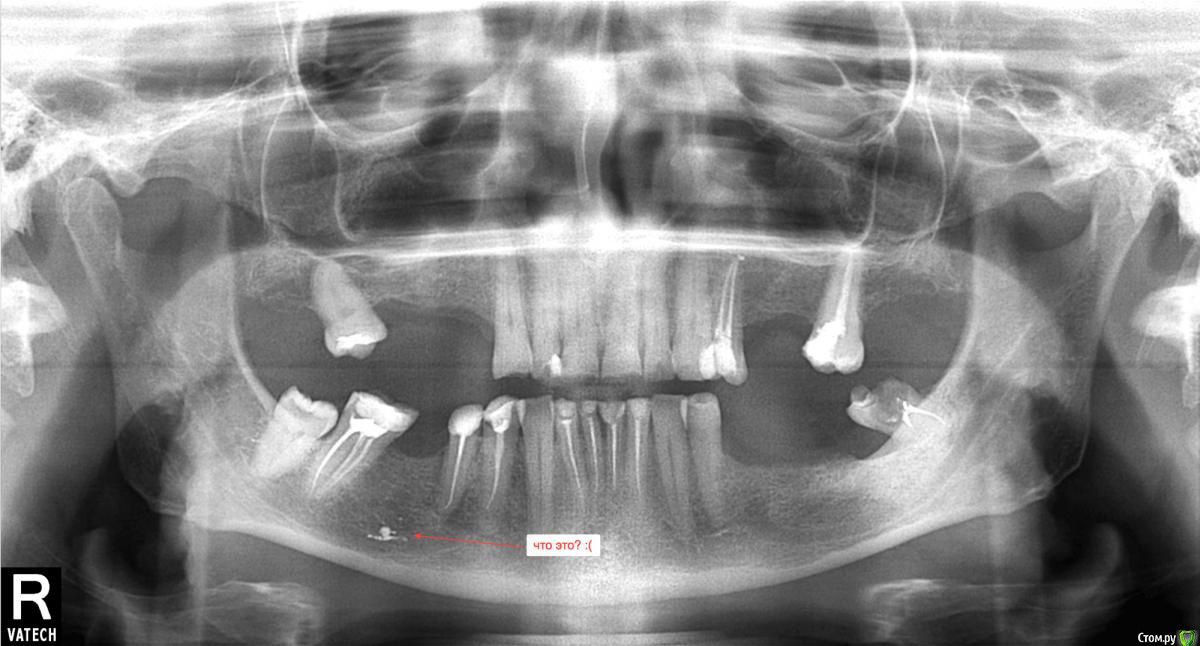

arinasmirn74@gmail.com Опубликовано 1 апреля, 2019 Поделиться Опубликовано 1 апреля, 2019 (изменено) Здравствуйте!Получила наконец панорамный снимок брата (планируется третий подход к снаряду после череды неудач, как то неудачная попытка съемного протезирования). Прошу прокомментировать, если возможно, этапность работ по восстановлению жевательной функции, варианты и что вообще делать? Передние без кариеса, но коронковая часть разрушена почти до десны, жевательных почти нет, что есть искривлено.Что может означать пятно в проекции давно удаленного зуба слева на снимке? Изменено 1 апреля, 2019 пользователем arinasmirn74@gmail.com Ссылка на комментарий

kramer Опубликовано 1 апреля, 2019 Поделиться Опубликовано 1 апреля, 2019 Пятно - пломбировочный материал. Если нужен несъемный протез, надо ставить имплантаты в боковых отделах. Зубы покрыть коронками. Ссылка на комментарий